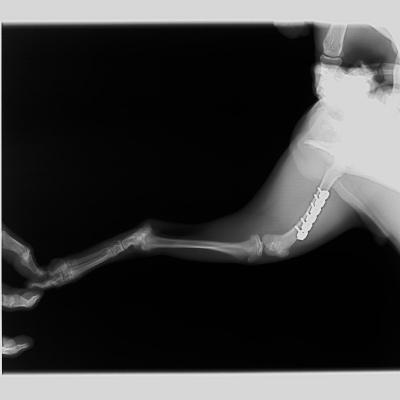

最初に紹介する写真は室内で転んで起きてしまった小型犬の橈尺骨(前足の骨)の骨折です。

骨折用の金属プレートを用いた手術によって、整復しました。